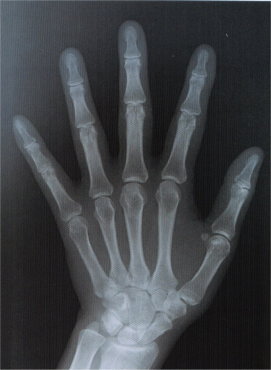

| 手の骨 | ![]() |

| 間違った経験談 | 拳を負傷した練習者に時として「拳の鍛え方が足りない」と教える指導者が居る。 手の骨格写真から明らかなとおり鉄より固い人間の骨が存在するとは理解出来ない。 骨粗鬆症の様に個人差も大きく存在する。 熟練者は痛めない様に打撃するのが巧くなってる可能性が高いだけ。 若い頃の経験だけで年齢を経てから自身が防具練習から離れており、運良く痛める前に保護していたのを恐らく忘れている。 |